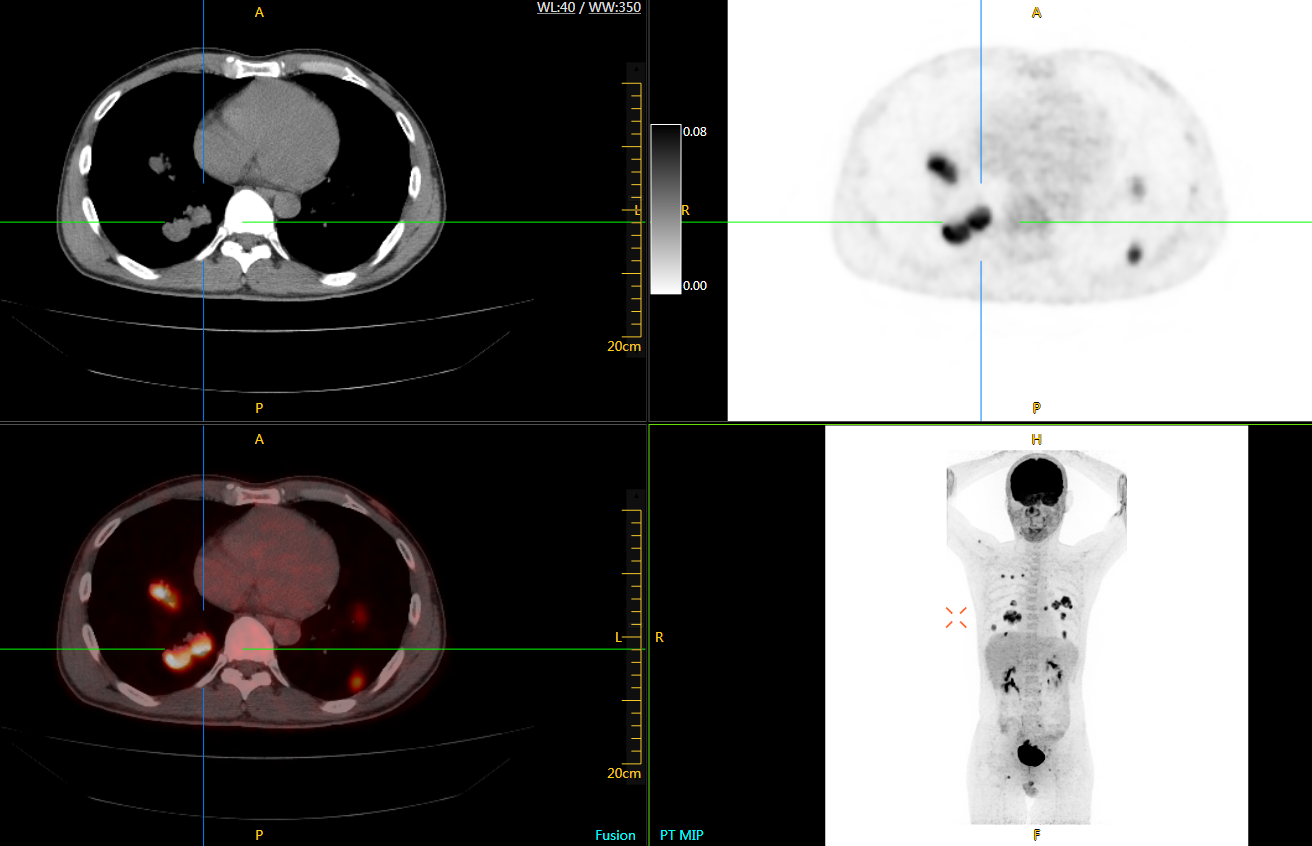

肺癌轉(zhuǎn)移及復發(fā)

患者男性,66歲,七年前發(fā)現(xiàn)右肺肺癌,其間手術兩次,共切除兩個肺葉,復查;

診斷意見,回腸轉(zhuǎn)移,右肺殘留部復發(fā)